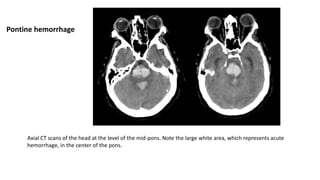

Axial CT scans of the head at the level of the mid-pons. Note the large white area, which represents acute

hemorrhage, in the center of the pons.

Pontine hemorrhage